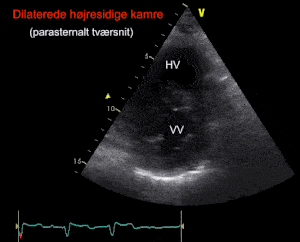

1) Akut højresidig belastning

Brugbare snit: Subcostalt, apikalt 4-kammer, parasternalt tværsnit

Hvis højre ventrikels tværdiameter er ligeså stor som venstre ventrikel eller større, er den med sikkerhed forstørret. Dette kan være tegn på fx lunge-emboli, men forstørrelse af de højre-sidige kamre kan også ses ved pulmonal hypertension af andre årsager, fx kroniske lungesygdomme.